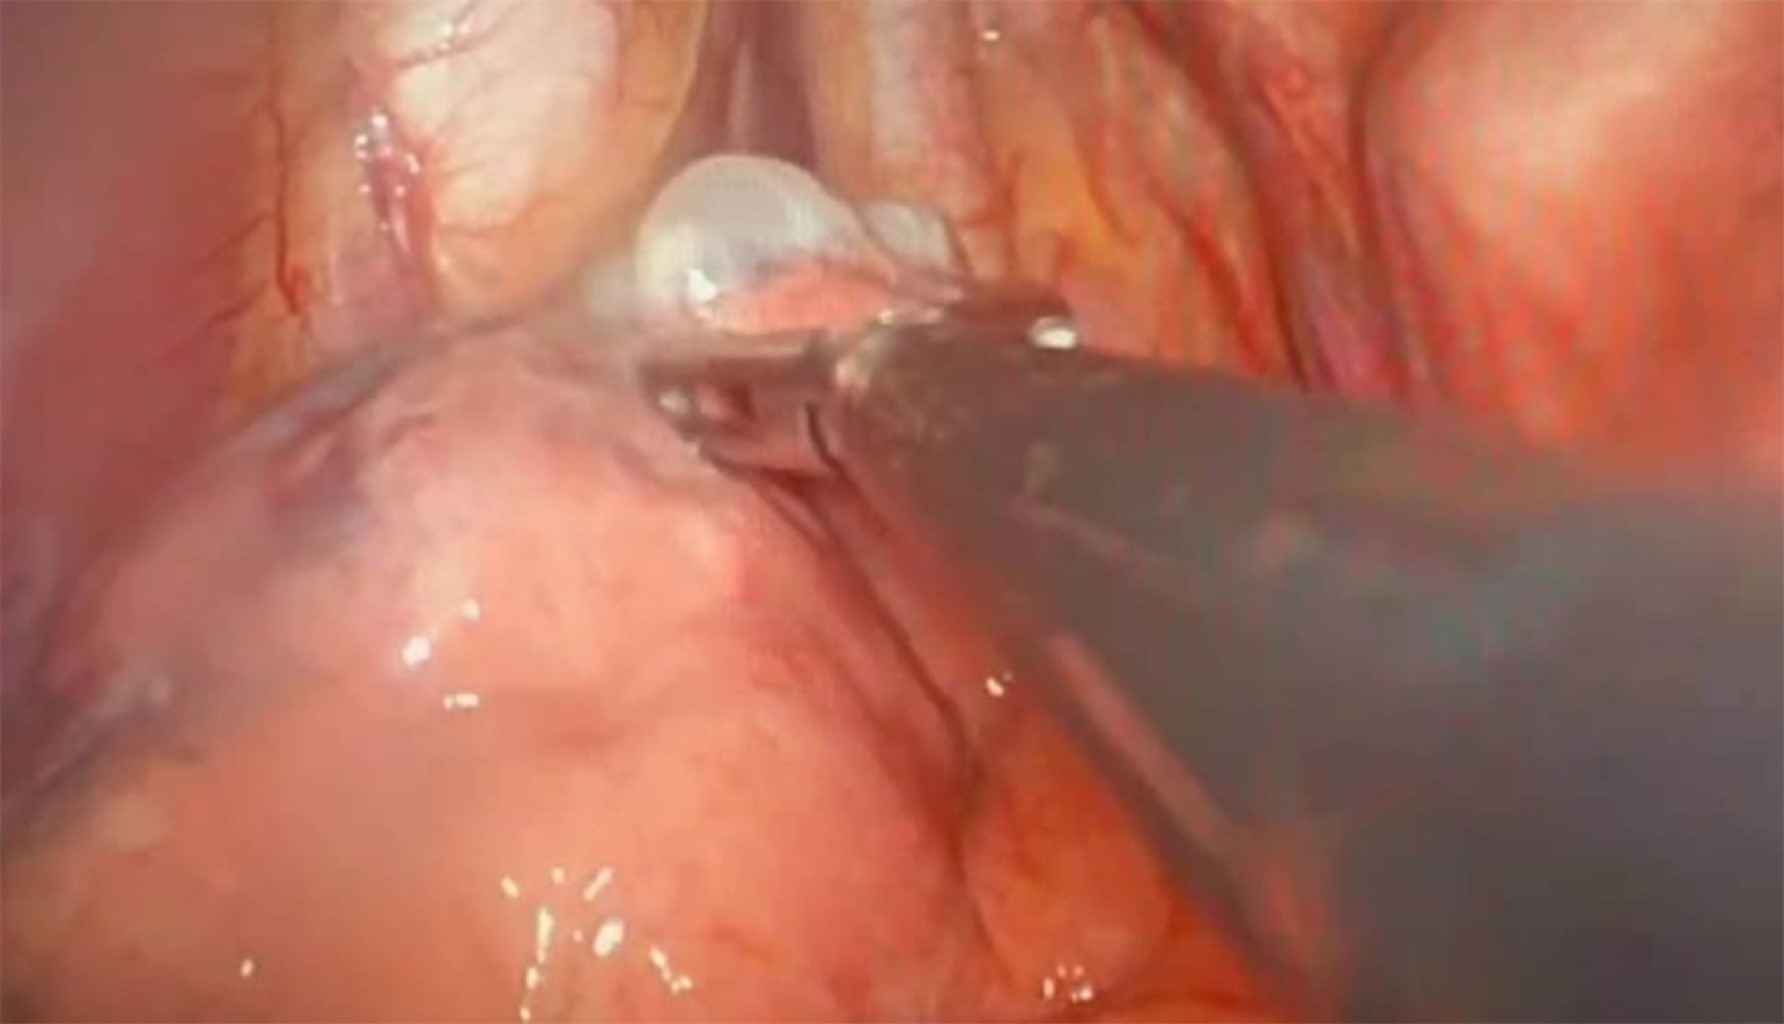

Las causas más comunes de enfisema bulloso incluyen el tabaquismo, la exposición a biomasa y la deficiencia de α-1 antitripsina. Los síntomas incluyen disnea progresiva, tos productiva, disminución de la tolerancia al ejercicio y sibilancias. Las opciones de tratamiento quirúrgico incluyen toracotomía o videotoracoscopia. Al elegir el abordaje ideal para cada paciente, se deben considerar la extensión y la ubicación de las bullas, las comorbilidades y el riesgo de recurrencia, entre otros factores. Presentamos dos casos quirúrgicos: una mujer de 45 años con antecedentes de exposición a biomasa y una bulla gigante que le causó dificultad respiratoria aguda, tratada con éxito mediante toracotomía; y un hombre de 25 años que desarrolló un neumotórax espontáneo con quistes subpleurales asociados con gran altitud, tratado mediante bullectomía videotoracoscópica.

Figura 2